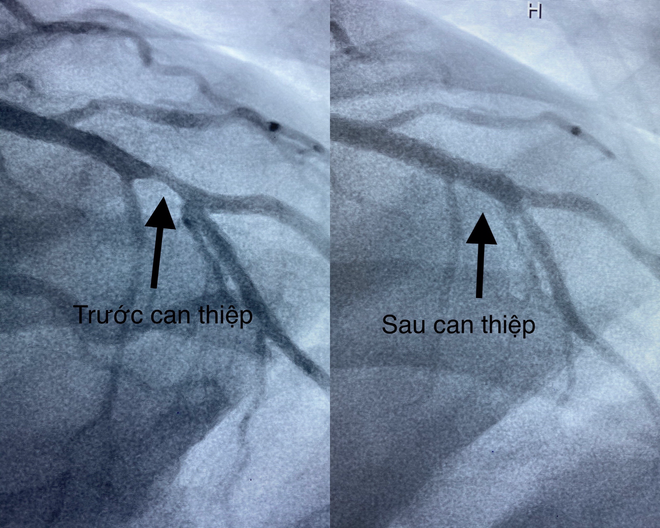

| Hình ảnh mạch vành của bệnh nhân bị hẹp nặng trước can thiệp và sau khi được đặt stent phủ thuốc tái thông mạch máu. Ảnh Đình Tuyển |

Bệnh nhân được chẩn đoán hôn mê, nhồi máu cơ tim cấp có biến chứng ngưng tim ngưng thở, suy hô hấp nặng. Sau khi được hồi sức tích cực, chụp CT sọ não kiểm tra và tiến hành can thiệp mạch vành cấp cứu. Kết quả chụp mạch vành cho thấy bệnh nhân bị hẹp nhánh liên thất trước đoạn II 80%, san thương không ổn định và can thiệp thành công bằng Stent phủ thuốc trong vòng 20 phút. Sau can thiệp, bệnh nhân được chuyển đến Khoa Hồi sức tích cực - Chống độc theo dõi và điều trị tiếp.